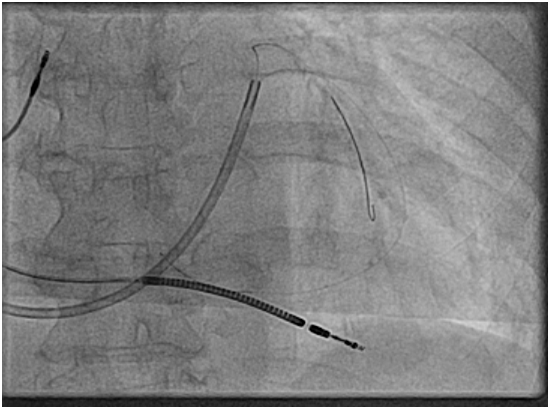

We admitted the patient, urgent interrogation of the device and changed in to (RV paced only) mode, with cessation of the abdominal twitches and the patient was completely comfortable and asymptomatic. Given she had significant symptomatic relief from shortness of breath after implantation we booked her for reposition of LV lead in the EP lab, balloon angioplasty of the coronary sinus lateral vein branch was done successfully and the lead was placed in a nice basal lateral position (Figures 3) (Figure 4). Then interrogation of CRTD with optimal results and normal post operative CXR (Figure 5).

Figures 3 Symptomatic relief from shortness of breath after implantation we booked her for reposition of LV lead in the EP lab.

Figure 4 Balloon angioplasty of the coronary sinus lateral vein branch was done successfully and the lead was placed in a nice basal lateral position.